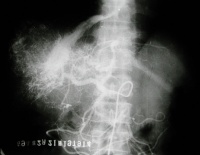

肝脏影像图